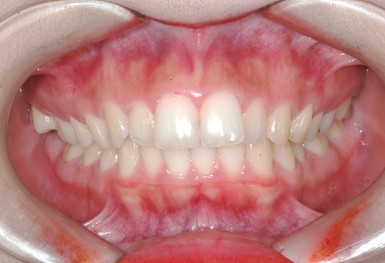

심한 덧니